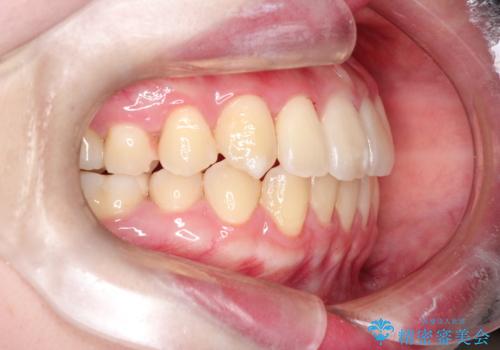

【インビザライン】歯を抜かずにできるだけ前歯を下げたい

- 前歯の前突を主訴に来院されました。

インビザライン を用いて、歯並びの改善を行うことができました。